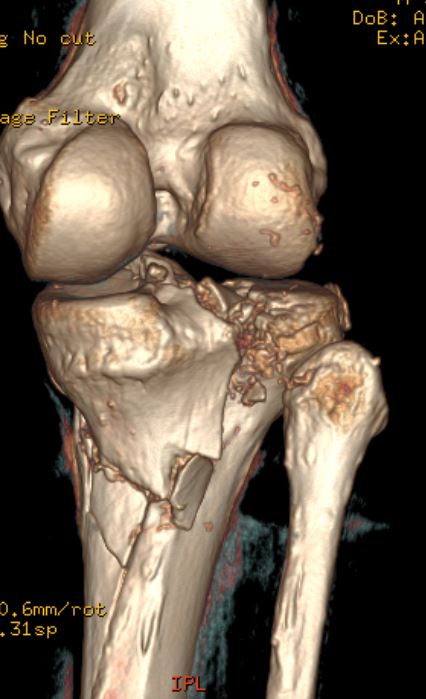

Das ist genau das große Problem, Kniegelenk ist zertrümmert, auch die Kreuzbänder, Kapsel und alles drumherum, ist schwer verletzt, hoffentlich kann ich es genug dehnen um weiter zu falten, jetzt bin ich nur bei 114° unter extremer Spannung, locker bin ich bei 104°, und übe schon vom 3-7-21, 3/Woche Fisio und den Rest 3 mal/Tag Hausübungen, hoffe bis April wieder fit zu sein um zu fahren... und Gute Nacht